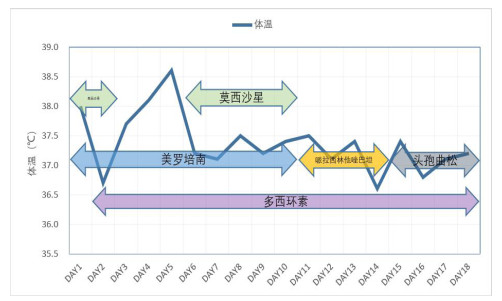

辅助检查:白细胞计数15.0×109/L,中性粒细胞百分比97.9%,淋巴细胞绝对值0.14×109/L,血小板计数344×109/L,血红蛋白94 g/L;降钙素原1.22 ng/mL,白介素6 87.5 pg/mL,C-反应蛋白254.5 mg/L;丙氨酸氨基转移酶171 U/L,天门冬氨酸氨基转移酶292 U/L,白蛋白24.7 g/L,肌酐186 μmol/L,尿素氮18.99 mmol/L,B型钠尿肽前体(pro brain natriuretic peptide, pro-BNP)3 301 pg/mL。胸部CT示两肺炎症渗出,左肺实变(图 1A)。经验性予美罗培南0.5 g每8 h一次联合莫西沙星400 mg每24 h一次抗感染治疗。行支气管镜检查留取肺泡灌洗液送痰培养和mNGS检测。在患者入院第2天,外周血mNGS检测到鹦鹉热衣原体,序列数166。改用美罗培南0.5 g每8 h一次(第1~10天)和多西环素片口服100 mg每12 h一次(第2~18天)抗感染治疗(图 2)。入院第3天的肺泡灌洗液mNGS回报鹦鹉热衣原体(序列数280)。痰培养、血培养、血隐球菌抗原、真菌G/GM试验均为阴性。入院第4天行腰椎穿刺检查,测得压力为240 mmH2O(1 cmH2O=0.098 kPa),脑脊液为无色透明,留取标本送常规、生化和mNGS。脑脊液结果提示有核细胞数为2×106/L,红细胞计数为22×106/L(参考范围 < 1×106/L),蛋白含量为34.8 mg/dL(参考范围8~43 mg/dL),葡萄糖含量为4.13 mmol/L(参考范围2.2~3.9 mmol/L)。入院第6天,脑脊液mNGS结果回报鹦鹉热衣原体(序列数4)。入院第8天复查腰椎穿刺的压力为185 mmH2O,留取标本送检。本次脑脊液常规和生化结果与第一次相仿,mNGS未检测到鹦鹉热衣原体。经过抗生素治疗(图 2),患者一般情况好转,炎症指标下降(图 3A、3B),脏器功能好转(图 3C、3D),复查胸部CT提示肺部病变吸收(图 1B),于入院第11天拔除气管插管改鼻塞吸氧,氧合99%,生命体征平稳。神志清,对答切题,语言流利,颈软。能稳准地完成指鼻试验和跟-膝-胫试验。于入院第18天出院。后随访患者恢复良好,无后遗症。住院期间头颅磁共振提示腔隙性缺血灶,未提示新发脑梗、脱髓鞘等病变(图 4)。患者出院后第5天和第44天查胸部CT见左肺渗出进一步吸收(图 1C、1D)。

| 莫西沙星400 mg 3次/d(第1~2天,第6~10天),美罗培南0.5 g每8 h一次(第1~10天),多西环素100 mg每12 h一次(第2~18天),哌拉西林他唑巴坦4.5 g每8 h一次(第11~14天),头孢曲松2 g 3次/d(第15~18天) 图 2 住院期间体温变化和抗生素方案 |

鹦鹉热的治疗药物有四环素类、大环内酯类和喹诺酮类[5, 23]。该患者在当地医院接受莫西沙星为主的方案治疗,期间疾病进展,提示该抗感染方案不能有效杀灭鹦鹉热衣原体。患者入本院后,使用美罗培南联合多西环素治疗,后加用莫西沙星协同治疗。患者入院后仅出现1次发热,CRP等炎症指标下降,肌酐、转氨酶、pro-BNP等代表脏器功能的指标趋于好转。在入院第8天,患者第2次腰椎穿刺脑脊液未找到鹦鹉热衣原体,提示美罗培南、多西环素和莫西沙星可有效杀灭中枢神经系统中的鹦鹉热衣原体。后期随访患者无明显后遗症。